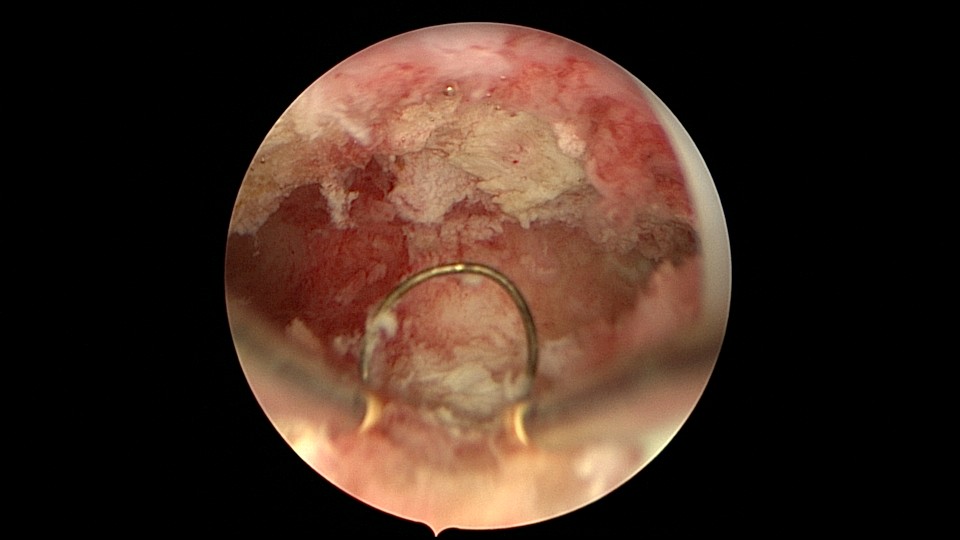

患者26岁,G7P1,剖宫产1次。2019年10月药流不全,行清宫术,术后闭经半年,后月经紊乱,周期28天~60天,月经量少。2021年4月,闭经50+天,B超提示宫腔粘连,宫腔镜见宫颈管上段封闭粘连,宫腔广泛粘连,AFS评12分(最高分)。宫腔镜电切分粘,恢复宫腔形态,显露双侧输卵管开口,宫腔防粘连复发处理,2021年5月宫腔镜二探取球囊。2021年7月自然妊娠,门诊人流并安环。2021年9月,月经推迟,B超提示宫腔粘连,节育环嵌顿,行宫腔镜取环并分粘,2021年10月二探取球囊。2021年12月放置皮埋避孕,2022年3月要求取出皮埋棒。2023年8月初自然妊娠,药流不全,2023年8月底行宫腔镜清除残留胚物。2024年2月自然妊娠10周,2024年4月初妊娠3+月(BPD2.6cm),坚决要求终止妊娠,行宫腔镜辅助终止妊娠。2025年6月因异常子宫出血再次宫腔镜分粘,2025年7月二探取球囊。现31岁,G10P1,前后共做了8次宫腔镜,术后多次自然妊娠,患者妊娠中途均选择了终止妊娠。